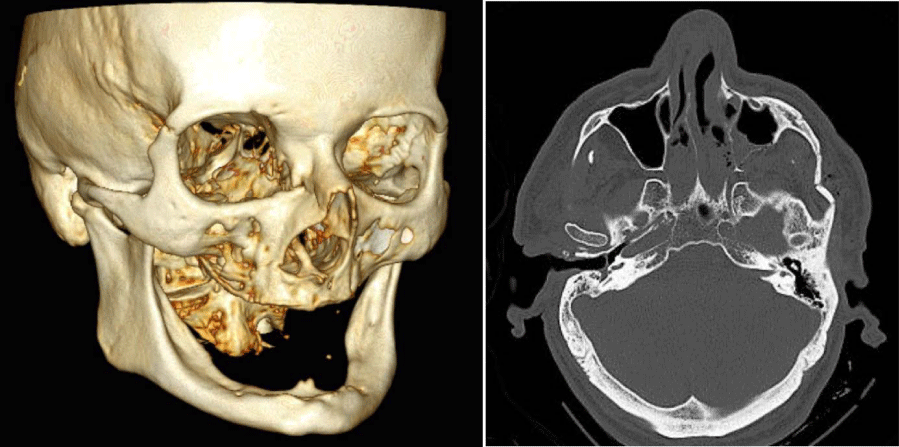

The zygoma - composed of woven bone - mostly cracks as tripod- or quadripod-fracture with lesser or major dislocations also of parts of the orbital-floor downwards and inwards relative to the maxillary sinus in vicinity to the foramen of the infraorbital nerve. Contrary to fractures of the long bones and the mandible the surfaces of the fractures show a very rough and uneven structure and the zygomatic arch does not always fracture necessarily due to the high elasticity of woven bone resulting in only a tripod-fracture stabilized by the zygomatic arch (Figure 4).

Figure 4:

Fracture pattern of the zygoma: red: infraorbital fracture-site, turquois: orbital-floor fracture-site, blue: fracture-site of the zygomatico-alveolar process, green: fracture-site of the lateral orbital rim, black: fracture-site in the zygomatic-arch; a) minimal dislocated quadripod-fracture beyond critical-size-defect dislocation (<2,7mm), b) dislocated quadripod-fracture above critical-size dislocation (> 2,7mm).

Although CAT-Scan diagnosis and 3D-reconstructions (Figures 3, 4 and 6) are valuable tools to determine the precise fracture -pattern, number of and distance between fracture-fragments and volume of intraorbital emphysema, they cannot replace a thorough clinical investigation by palpation and functional analysis of the eye-bulbs and stomathognathic system which has to take place firsthand.